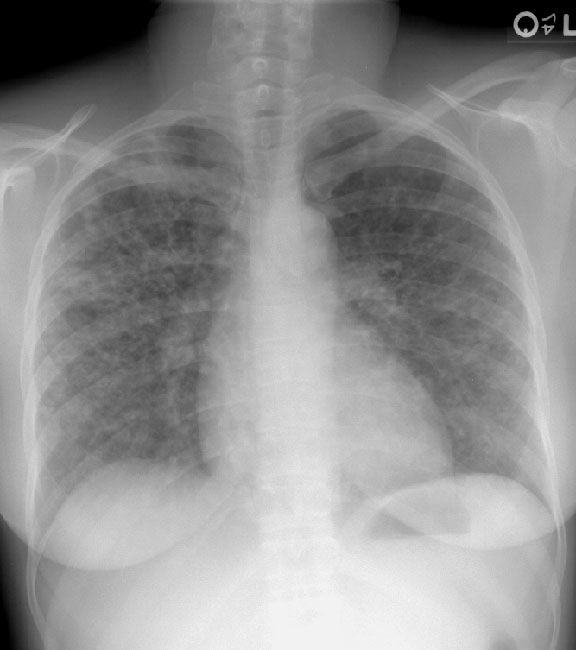

Scott WilliamsAutoimmuneAutoimmune > Sarcoid > Images > Sarcoid3April 2, 2002Central Nervous SystemCNS > CSF imagingApril 2, 2002PETPET Myocardial ImagingApril 2, 2002CardiacCardiac > Adultdz > ProstheticApril 2, 2002Pulmonary ImagingGeneral > BiopsyApril 2, 2002AutoimmuneAutoimmune > Wegener > Images > Case1April 2, 2002Vascular AbnormalitiesVascular > PE > Images > Iliac DVTApril 2, 2002GastrointentinalGastrointestinal > Hepatobiliary > Biliary atresiaApril 2, 2002AutoimmuneAutoimmune > FollbronchApril 2, 2002AutoimmuneAutoimmune > EGApril 2, 2002Previous PagePage 108 of 265Next PageTop StoriesCT5-year CTC screening interval is appropriate for colorectal cancerThe study's findings add to an ongoing conversation about the use of CTC for colorectal cancer screening.MRIASTRO: Daily MRgRT recontouring improves prostate treatment outcomesRadiation Oncology/TherapyASTRO: Radiation therapy comparable to surgery for early-stage lung cancerCTCT use in the ED has more than doubled over a decadeSponsor ContentDigital Innovations Shaping the Future of Radiology